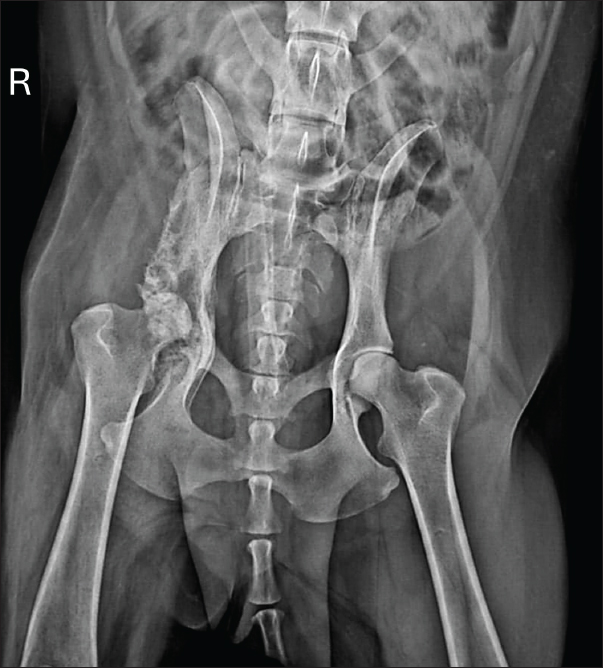

Radiographic examination revealed marked periosteal bone proliferation with extensive areas of osteolysis affecting the wing and body of the ilium, acetabulum, and right femur’s head and neck, along with adjacent soft tissue swelling (Fig. 1).

Fig. 1. Radiographic examination of the dog showing periosteal bone proliferation and areas of osteolysis (arrows) in the right wing and body of the ilium and acetabulum, accompanied by adjacent soft tissue swelling.